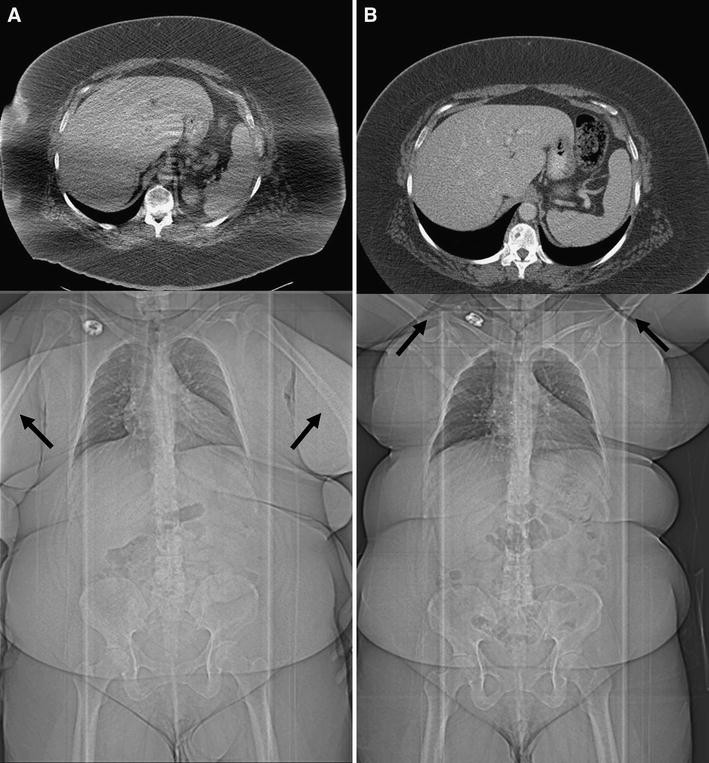

"But even if you have trouble getting one person on the machine, this is a problem," he said. People are considered obese when their body mass index (BMI), a measurement obtained by dividing a person's weight in kilograms by the square of the person's height in meters, exceeds 30 kg/m2 Radiographs are limited by X-ray beam attenuation that results in lower image contrast

XRay Body Fat Skin by Design Dermatology & Laser Center, PA. The radiographic technique requires adjustment for accurate results It provides a more accurate measure of body fat proportion than weight alone, but due to these limitations it may incorrectly under, or overestimate measurements in certain people.11-13 This point aside, BMI is widely accepted in the literature, including the limited literature in medical imaging, as a good descriptor of obesity at a.